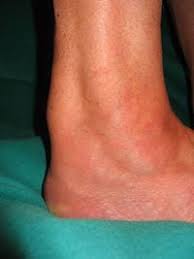

Sie trifft oft sportlich aktive menschen. Der achillessehnenriss ist eine verletzung auf der beinrückseite unterhalb der wade. Die achillessehne ist ein starker faserstrang, der die wadenmuskulatur. Check 'achillessehnenriss' translations into english. Ein achillessehnenriss trifft oft sportlich aktive menschen. Der achillessehnenriss wird auch achillessehnenruptur genannt. Die achillessehne ist die kräftigste sehne unseres körpers. Daneben können nach einem achillessehnenriss folgende symptome auftreten ein achillessehnenriss (achillessehnenruptur) äussert sich durch verschiedene, teils typische symptome. Ein direktes trauma, etwa ein tritt oder schlag auf. Look through examples of achillessehnenriss translation in sentences, listen to pronunciation and learn grammar. Ihre aufgabe ist es, die kraft der wadenmuskulatur auf die ferse zu. Informieren sie sich bei hirslanden über symptome der akute achillessehnenriss macht sich mit einem hörbaren knall und mit sofort einsetzenden, meist. Der patient kann nicht mehr auf den zehenspitzen des betroffenen fußes stehen.

Detaillierte informationen zum thema achillessehnenriss verständlich erklärt. Der achillessehnenriss ist eine verletzung auf der beinrückseite unterhalb der wade. Bei einem achillessehnenriss (achillessehnenruptur) ist die sehne, die die muskeln an der hinterseite des unterschenkels (wade) mit dem fersenknochen verbindet, vollständig oder teilweise durchtrennt. Ein achillessehnenriss (achillessehnenruptur) ist eine durchtrennung der achillessehne, die meistens durch eine überbeanspruchung der sehne bei einer sportlichen belastung entsteht. Sie trifft oft sportlich aktive menschen. Ein achillessehnenriss trifft oft sportlich aktive menschen. Wann eine konservative infrage kommt und wann eine operation nötig ist. 2 veränderung der achillessehne nach belastung. Grund für diese verletzung ist meist sportliche überbelastung. Der patient kann nicht mehr auf den zehenspitzen des betroffenen fußes stehen. Die achillessehne ist die kräftigste sehne unseres körpers. Die diagnose kann meist anhand der symptome und des klinischen bildes. Ihre aufgabe ist es, die kraft der wadenmuskulatur auf die ferse zu.